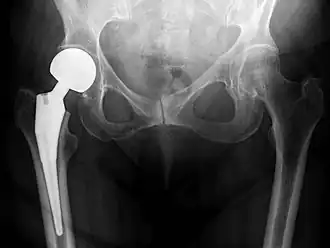

Post-operative projectional radiography is routinely performed to ensure proper configuration of hip prostheses.

The direction of the acetabular cup influences the range of motion of the leg, and also affects the risk of dislocation.[16] For this purpose, the acetabular inclination and the acetabular anteversion are measurements of cup angulation in the coronal plane and the sagittal plane, respectively.

![Acetabular inclination.[95] This parameter is calculated on an anteroposterior radiograph as the angle between a line through the lateral and medial margins of the acetabular cup and the transischial line which is tangential to the inferior margins of the ischium bones.[95]](./Acetabular_inclination_of_hip_prosthesis.jpg)

![Acetabular inclination is normally between 30 and 50°.[95] A larger angle increases the risk of dislocation.[16]](./Range_of_acetabular_inclination.png)